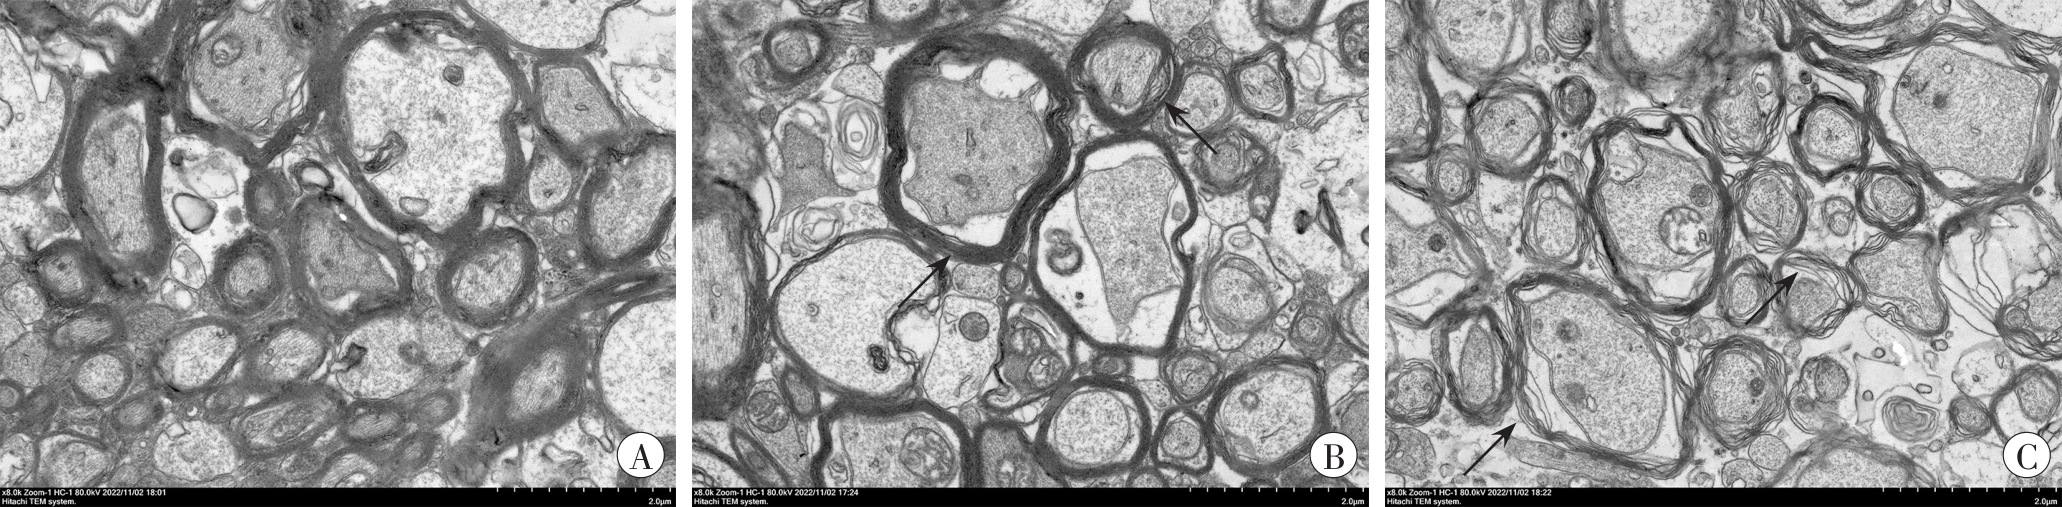

目的 探讨一氧化碳(carbon monoxide,CO)中毒致小鼠脑白质损伤部位神经细胞铁代谢变化及肠道菌群紊乱引起机体铁离子吸收异常的可能机制。 方法 将C57BL/6小鼠置于密闭广口瓶中给予CO气体制作CO中毒小鼠模型,正常对照组予相同处理但不给予CO气体。对小鼠脑白质部位取材,观察脑白质的形态学改变,通过免疫组织化学和蛋白质印迹法分析转铁蛋白(transferrin,TRF)和谷胱甘肽过氧化物酶4(glutathione peroxidase 4,GPX4)的表达变化。同时,于小鼠染毒后3 d和7 d收集粪便,进行16S rRNA测序,分析CO中毒引起的小鼠肠道菌群变化。 结果 电镜结果显示,CO中毒导致小鼠脑白质出现明显脱髓鞘,TRF表达升高(P<0.05),GPX4表达降低(P<0.05)。CO中毒导致小鼠肠道菌群分布异常,致肠组织铁离子吸收异常。 结论 CO中毒可导致脑白质神经细胞损伤,进而导致脱髓鞘病变,也可引起小鼠肠道菌群分布和铁离子吸收异常。